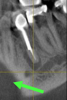

Fig. 27 through Fig. 30 The radiograph shows a periapical radiolucency. Three slices from the CBCT show a clear root fracture and buccal fistula showing an unrestorable tooth. With the CBCT information, the doctor can explain alternatives to the patient and not be surprised at the time of surgery.

Figure 27

Figure 28

Figure 30

Manufacturers have introduced CBCT systems with a smaller field of view, which reduces exposure, and is ideal for endodontics, in which the area of interest is usually one or two teeth.14 Three-dimensional imaging has been shown to be effective for helping the clinician find additional canals and certain types of root fracture as well as to visualize radiolucencies around teeth (Figure 22, Figure 23, Figure 24, Figure 25, Figure 26, Figure 27, Figure 28, Figure 29 and Figure 30).15 CBCT data provide additional diagnostic information about blocked canals, strip perforations, and proximal bone loss, which leads to appropriate treatment, ultimately saving patients from failed procedures and associated costs (Figure 31 and Figure 32).16